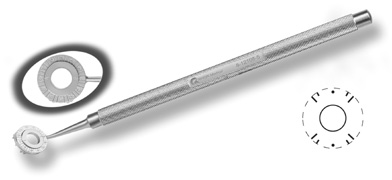

The extent of arc to be incised may be demarcated in several different ways. Our preferred method makes use of a modified Fine-Thornton fixation ring (Nichamin Fixation Ring and Gauge; Mastel Precision, Storz, Rhein Medical). This instrument serves to fixate and position the globe in order to optimize incision placement, as well as to delineate the extent of arc to be incised. One visually extrapolates from the limbus to marks on the surface of the ring. Each incremental mark is 10 degrees apart, and bold hash marks (180 degrees) opposite to each other serve to align and center the incision over the steep meridian. This approach obviates the need to ink and physically mark the cornea. If one desires, particularly when first gaining experience with LRIs, a two-cut RK marker may be used to place ink marks upon the cornea to show the exact extent of arc that is to be incised, in conjunction with the fixation ring/gauge (Fig. 4). Alternatively, various press-on markers are available, such as those made by Rhein Medical (Dell-Nichamin Marker, Nichamin-Kershner Marker, or the Ruminson Marker) (Fig. 5). ASICO and other instrument companies offer a full line of dedicated markers, rings, and blades for performing LRIs.

Fig. 4. The Nichamin Fixation Ring and Gauge serves to both fixate the globe and delineate the extent of arc to be incised; a two-cut radial marker may be used to mark the extent of arc to be incised, and the Mastel Nichamin Force AK Diamond Blade with preset depth of 600 microns.